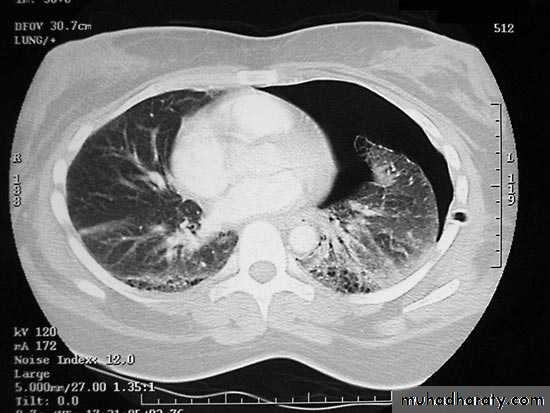

Chest X-ray;Shows the sharply defined edge of the deflated lung with complete translucency (no lung markings) between this and the chest wall. Chest X-rays also show the extent of any mediastinal displacement and give information regarding the presence or absence of pleural fluid and underlying pulmonary disease.

CT of chest;

Is useful in distinguishing bullae from pleural air.